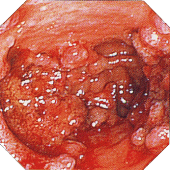

| ■診断基準 次のa)のほか、b)のうちの1項目、およびc)を満たし、下記の疾患が除外できれば、確診とする。 a)臨床症状:持続性または反復性の粘血・血便、あるいはその既往がある。 b)@内視鏡検査:i)粘膜はびまん性におかされ、血管透見像は消失し、粗像または細顆粒状を呈する。さらに、もろくて易出血性(接触出血)を伴い、粘血膿性の分泌物が付着しているか、ii)多発性のびらん、潰瘍、iii)偽ポリポーシスを認める。 A注腸X線検査:i)粗ぞうまたは細顆粒状の粘膜表面のびまん性変化、ii)多発性のびらん、潰瘍、iii)偽ポリポーシスを認める。その他、ハウストラの消失(鉛管像)や腸管の狭小・短縮が認められる。 c)生検組織学的検査:活動期では粘膜全層にびまん性炎症細胞浸潤、陰窩膿瘍、高度な杯細胞減少が認められる。緩解期では腺の配列異常(蛇行・分岐)、萎縮が残存する。 上記変化は通常直腸から連続性に口側にみられる。 b)c)の検査が不十分、あるいは施工できなくとも、切除手術または剖検により、肉眼的および組織学的に本症に特徴的な所見を認める場合は、下記の疾患が除外できれば、確診とする。 除外すべき疾患は、細菌性赤痢、アメーバ赤痢、サルモネラ腸炎、キャンピロバクタ腸炎、大腸結核などの感染性腸炎が主体で、その他にクローン病、放射線照射性大腸炎、薬剤性大腸炎、リンパ濾胞増殖症、虚血性大腸炎、腸型ベーチェットなどがある。 注1)まれに血便に気付いていない場合や、血便に気付いてすぐ来院する(病悩期間が短い)場合もあるので注意を要する。 注2)所見が軽度で診断が確実でないものは「疑診」として取り扱い、後日再燃時などに明確な所見が得られた時に本症と「確診」する。 棟方昭博:厚生省特定疾患難治性炎症性腸管障害調査研究班 平成9年度研究報告書

■活動期内視鏡的所見による分類

注12)内視鏡的に観察した範囲で最も所見の強いところで診断しする。 内視鏡検査は前処置なしで短時間で施行し、必ずしも全大腸を観察する必要はない。 棟方昭博:厚生省特定疾患難治性炎症性腸管障害調査研究班 平成9年度研究報告書